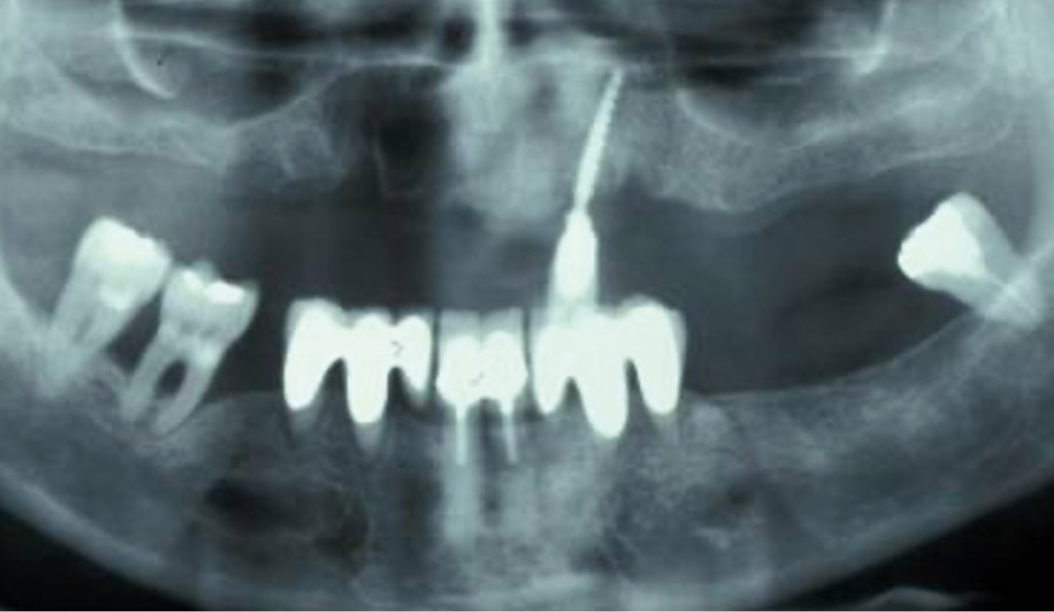

Peri-implant mucositis can be defined as an inflammatory lesion of the soft tissues (mucosa) surrounding the dental implant. Peri-implantitis is an inflammatory lesion of the mucosa affecting the supporting bone (crestal bone) with crestal bone loss and loss of osseointegration. Derks et al. report a prevalence of 43% for peri-implant mucositis and Jepsen et al. estimate that the prevalence of peri-implantitis could reach 22% (Figs. 1, 2).2,3 Peri-implantitis is usually accompanied by crestal bone loss (Fig. 3) and soft tissue changes in the peri-implant sulcus, which can be diagnosed by an increase in bleeding on probing (BOP) more than 5mm over previous examinations and/or suppuration8 (Fig. 4). Also excess of residual cement might contribute to crestal bone loss (Fig. 5).7

The underlying inflammatory processes are still not completely understood. However, increasing evidence shows that the host and the peri-implant conditions might play a pivotal role in the development of peri-implantitis (Figs. 1, 2).2,3

Based on current evidence and studies suggesting that zirconia dental implants are associated with less peri-implant inflammatory reactions and less crestal bone loss (Fig. 7), we decided to investigate the behavior, the mechanical stability and the clinical outcomes of ceramic implants at our institution. The first patient implantations look promising. But long-term studies will be required to develop strong evidence and convince the large majority of dental implant surgeons to use zirconia dental implants as routinely as orthopedic surgeons do in hip replacement.